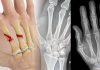

Rolando kırığı, başparmak metakarp kaidesinin eklem içi çok parçalı kırığıdır; “T” veya “Y” şeklinde olan tipleri ile karşımıza çıkar. Ayrılmamış kırıklarda alçı tespit için yeterliyken, ayrılmış kırıklarda açık redüksiyon internal fiksasyon tekniği kullanılmaktadır.